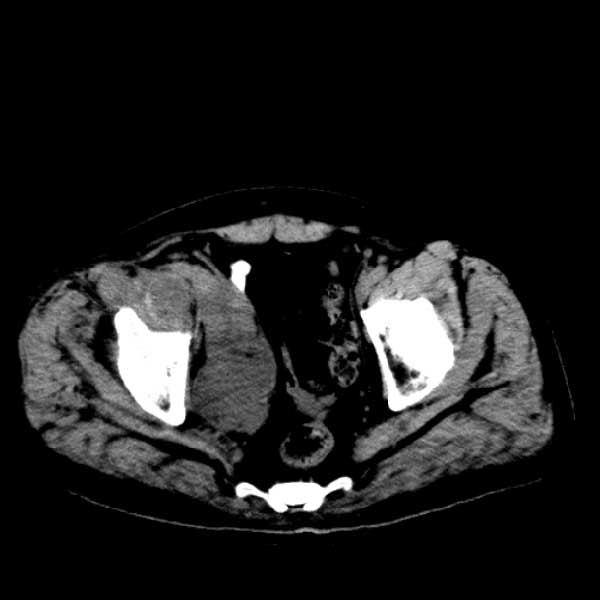

标题: CT13513:男 71 腹部疼痛20余天,近几天高热就诊,骨窗未见异 [打印本页]

标题: CT13513:男 71 腹部疼痛20余天,近几天高热就诊,骨窗未见异

考虑感染性病变可能性大,起源于阑尾?

考虑为化脓性阑尾炎.脓肿形成.及多肌肉累及.

考虑右侧腰大肌脓肿,向右髂窝、右腹股沟流注。

支持化脓性阑尾炎伴右髂窝脓肿、腰大肌腰方肌脓肿形成。

考虑腹腔及盆腔化脓性炎症,累及右侧髋关节及腹股沟区.

首先考虑化脓性阑尾炎伴腰大肌、腰方肌脓肿,不除外回盲部结核。

回盲部癌待排除。

患者肠镜检查考虑结肠癌,病理证实

患者肠镜检查考虑结肠癌,病理证实。肺部ct可见多发结节,考虑转移